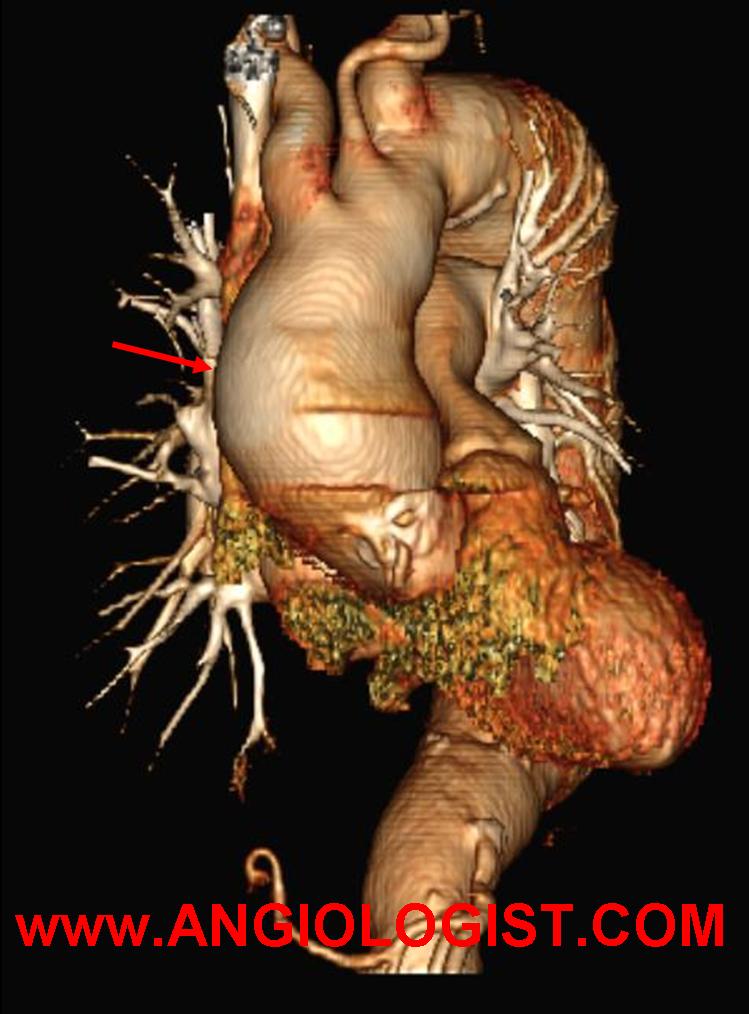

- Large artery involvement (aortic arch syndrome) alone or in conjunction with the other clinical manifestations of giant cell arteritis is typical. An aortic aneurysm can be diagnosed years after the disease has manifested. Still, it is not clear how to screen for aortic involvement, how often and for how long. Less commonly, other large arteries may be involved. For instance, the lower extremity arteries.

- Computed tomography – CT with contrast can be useful both for the diagnosis of arterial inflammation and for the diagnosis of possible vascular complications of giant cell arteritis.

As I wrote above, aneurysms can be a complication of the inflammatory process. Surgical resection of these aneurysms has been described with good overall results. The aneurysms may be a remnant of past disease or present during active phases. If the disease is active, surgery should be postponed, if possible, until the inflammation cools off. Anti-inflammatory medication is sometimes added after surgery The timing of this treatment after surgery is unclear, as early treatment may interfere with healing, while late treatment may expose patients to further complications.